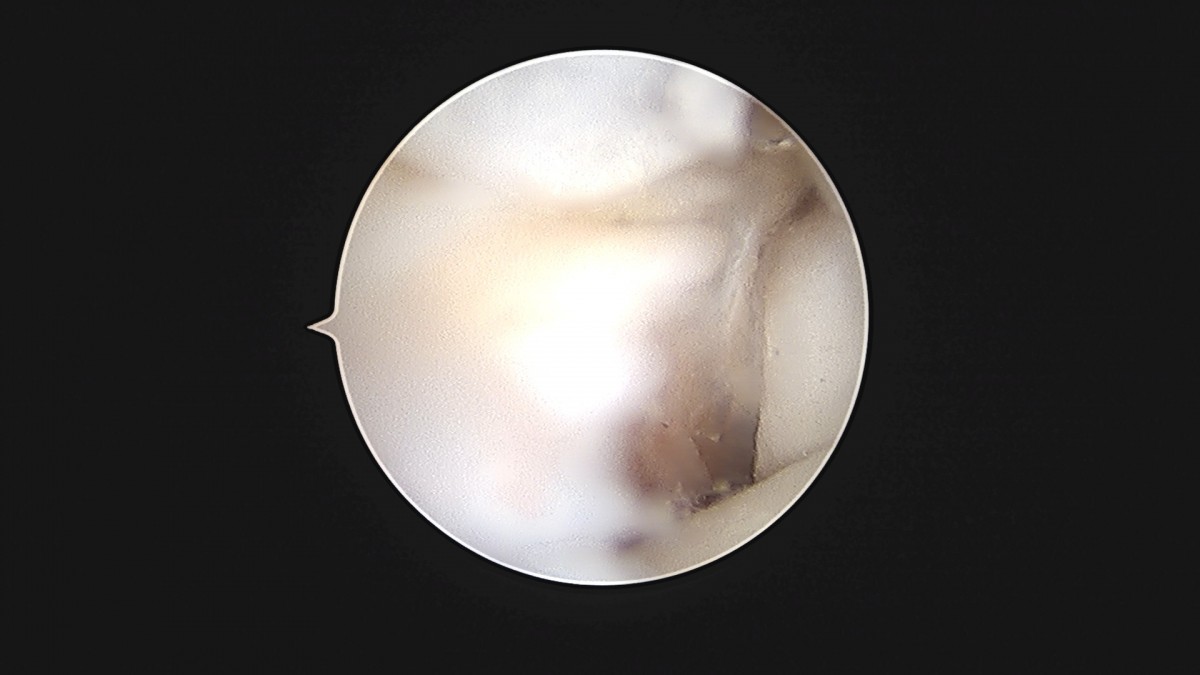

이재상원장님 발목 활액막 절제술 및 인대 봉합술 신진O 환자

dae765e4d9ac96aee867c9d6292d8784_1758003731_8482.jpg